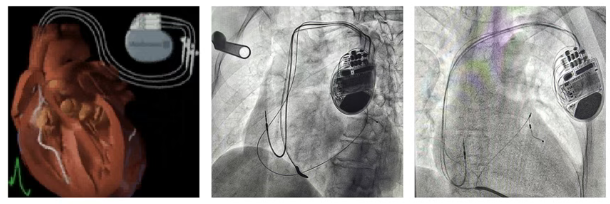

扬子晚报网3月26日讯(通讯员 刘柳 记者 姜天圣)日前,镇江瑞康医院心内科在首席专家严金川教授指导下完成镇江首例房室结消融+CRT-D术,成功救治一名扩张型心肌病合并快速房颤、心力衰竭的危重患者。

该患者是一名66岁女性,有房颤、心衰病史10余年,病情反复发作。在外院多次就诊未解决病痛,经多方打听,慕名找到严金川教授。瑞康医院心内科团队经仔细检查发现:患者心脏极度扩大(左室舒张末期内径72mm)、完全性左束支(QRS-175ms)、快速房颤、严重心力衰竭(EF: 20%),病情十分危重,随时可能猝死。严金川教授带领团队根据最新医学指南并综合患者病情,制定了CRT-D+房室结消融最佳手术方案。经过3小时成功完成手术,术后各项监测指标良好,症状得到了明显缓解,患者转危为安。

据介绍,CRT-D术结合了CRT(心脏再同步化治疗起搏器)和ICD(埋藏式心脏自动除颤器)的双重功能,最大的特点是在治疗心脏功能衰竭、让扩大的心脏回缩的同时,防止因恶性心律失常导致的猝死,主要适用于完全性左束支伴心肌病或冠心病合并心衰及有猝死高危风险的患者。

房室结消融术的目的是消除房颤自身不规则且快速的电信号干扰、抑制CRT-D的起搏指令。消融后这种干扰被彻底消除,CRT-D能时刻掌控心跳,实现最理想的同步治疗。此次CRT-D+房室结消融术的成功实施,标志镇江瑞康医院心内科处理复杂、危重心脏病患者的能力迈上了新的台阶。